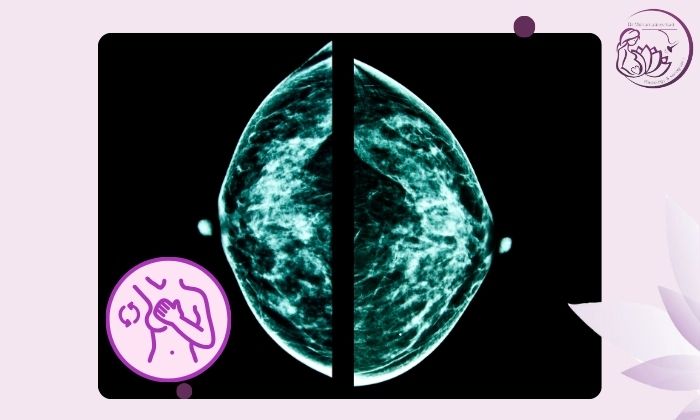

در ادامه برخی از تصاویر مامو این مرکز را می توانید مشاهده کنید.